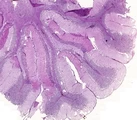

![]() | obrzęk jelita | 50%